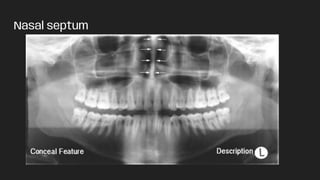

● Nasal septum

Nasal septum